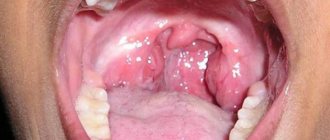

The photo on the right shows the most important symptom of lacunar tonsillitis: purulent plaque on the tonsils

Local status of lacunar angina, patients experience some symptoms:

• redness and inflammation of the palatine arches, tonsils;

A specific sign of this form of sore throat is a yellow-white coating in the form of foci or a continuous film. If left untreated, it becomes purulent. The plaque is easily removed, and the mucous membrane does not bleed.

An examination of the pharynx allows one to identify signs characteristic of lacunar tonsillitis: pronounced infiltration and swelling of the palatine tonsils, accumulation in the lacunae of yellowish islands of purulent contents and films covering the surface of the tonsil. When removing the films with a spatula, they come off relatively easily without damaging the underlying tissue or causing bleeding.

There is usually no runny nose. The patient has weakness and no appetite, often has a headache, and the lymph nodes become inflamed. If you examine the oropharynx, you will notice swelling of the mucous membranes and hyperemia. In the lacunae there is a purulent plaque of white or grayish color.